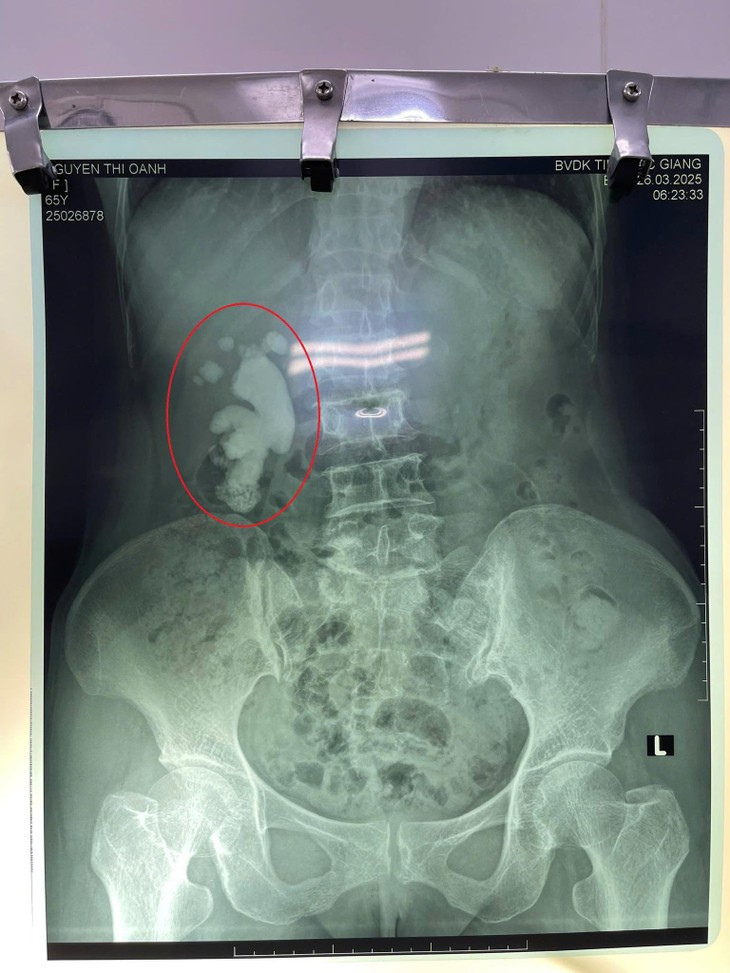

| Kết quả chụp CT cho thấy hình ảnh sỏi san hô thận phải. Ảnh BVCC |

Trong quá trình thực hiện phẫu thuật, các bác sĩ đã loại bỏ toàn bộ sỏi trong lòng bể thận, có nhiều sỏi san hô lớn, dài, khối lớn dài nhất tương đương với 1 ngón tay người trưởng thành, hình dạng như củ gừng và nhiều sỏi vụn.